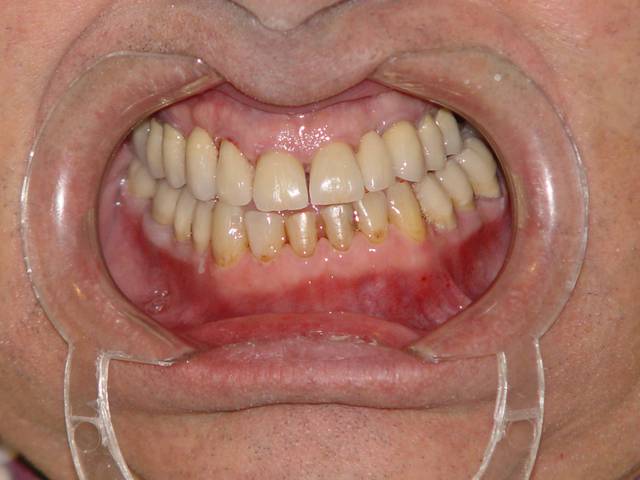

de retour au cabinet je peux vous poster les différentes étapes de ce que j'ai réalisées pour ce patient dans le cadre de l'OSB afin de me faire mousser et non de partager avec vous une expérience qui m'a parue intéressante comme alternative à la cavalerie lourde proposée par certains d'entre vous à savoir la chirurgie...

Tout d'abord évaluation de la hauteur d'occlusion fonctionnelle à l'aide de cire à boxer on laisse le patient avaler sa salive pendant 10 mn, puis arc facial et montage sur articulateur Artex, wax up et reconstitution prothétique temporaire des dents postérieures.

voilà les photos excusez moi d'en avoir doublé une, , quant à la dernière, c'est celle de la semaine dernière.